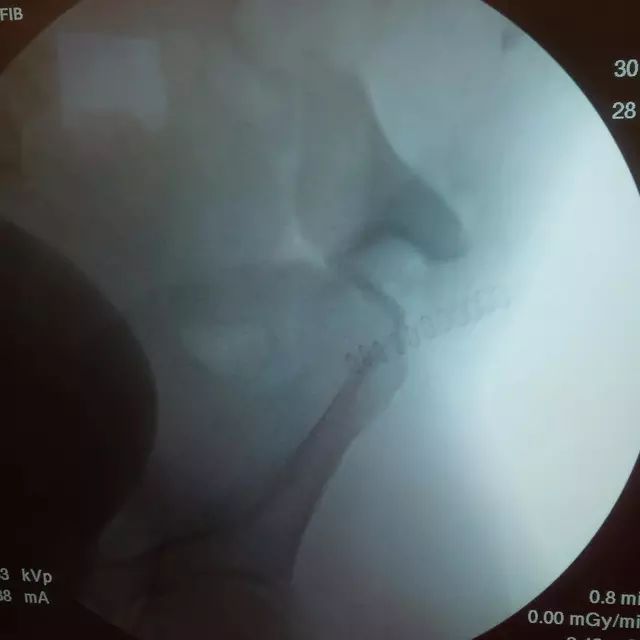

胫骨远端开放性骨折,远端骨折块游离在体外

游离骨块浸泡在抗生药物生理盐水溶液中

X 线片可见骨块寄养在自体下腹部皮下

创口清创、大量冲洗以后一期外固定支架固定,缺损区域抗生素骨水泥填充

二期回植,更换为钢板内固定

回植后 8 个月,骨折无感染迹象